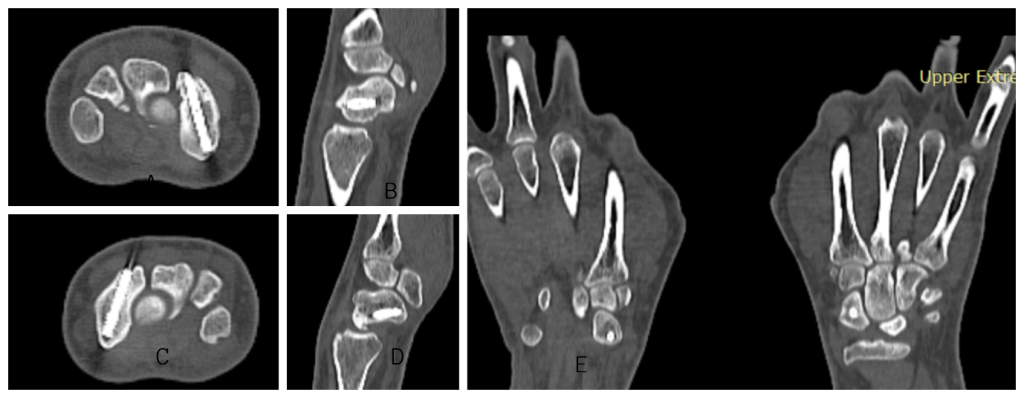

Figure 2: Computed tomography (CT) of left wrist showing scaphoid fracture in coronal (a), sagittal (b), and axial (c) sections. CT of right wrist showing scaphoid fracture in axial (d), sagittal (e), and coronal (f) sections.